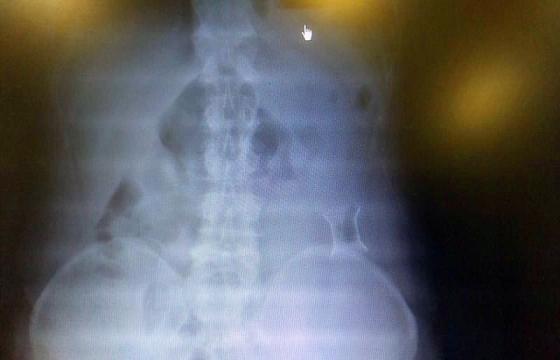

受試患者在結腸端端吻合術中,使用我司新研制產(chǎn)品達到了理想的預期效果?;颊咝g后7天、14天X光片顯影,可降解腸道支架均能按研制設計的預期時間節(jié)點保持應有強度,術后21天X光片顯示可降解腸道支架已完全破碎,并排出體外。在整個試驗過程中,病患無任何不良反映,耐受良好。